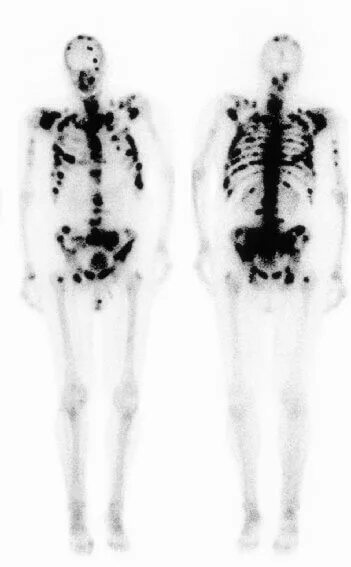

Метастазы скелета